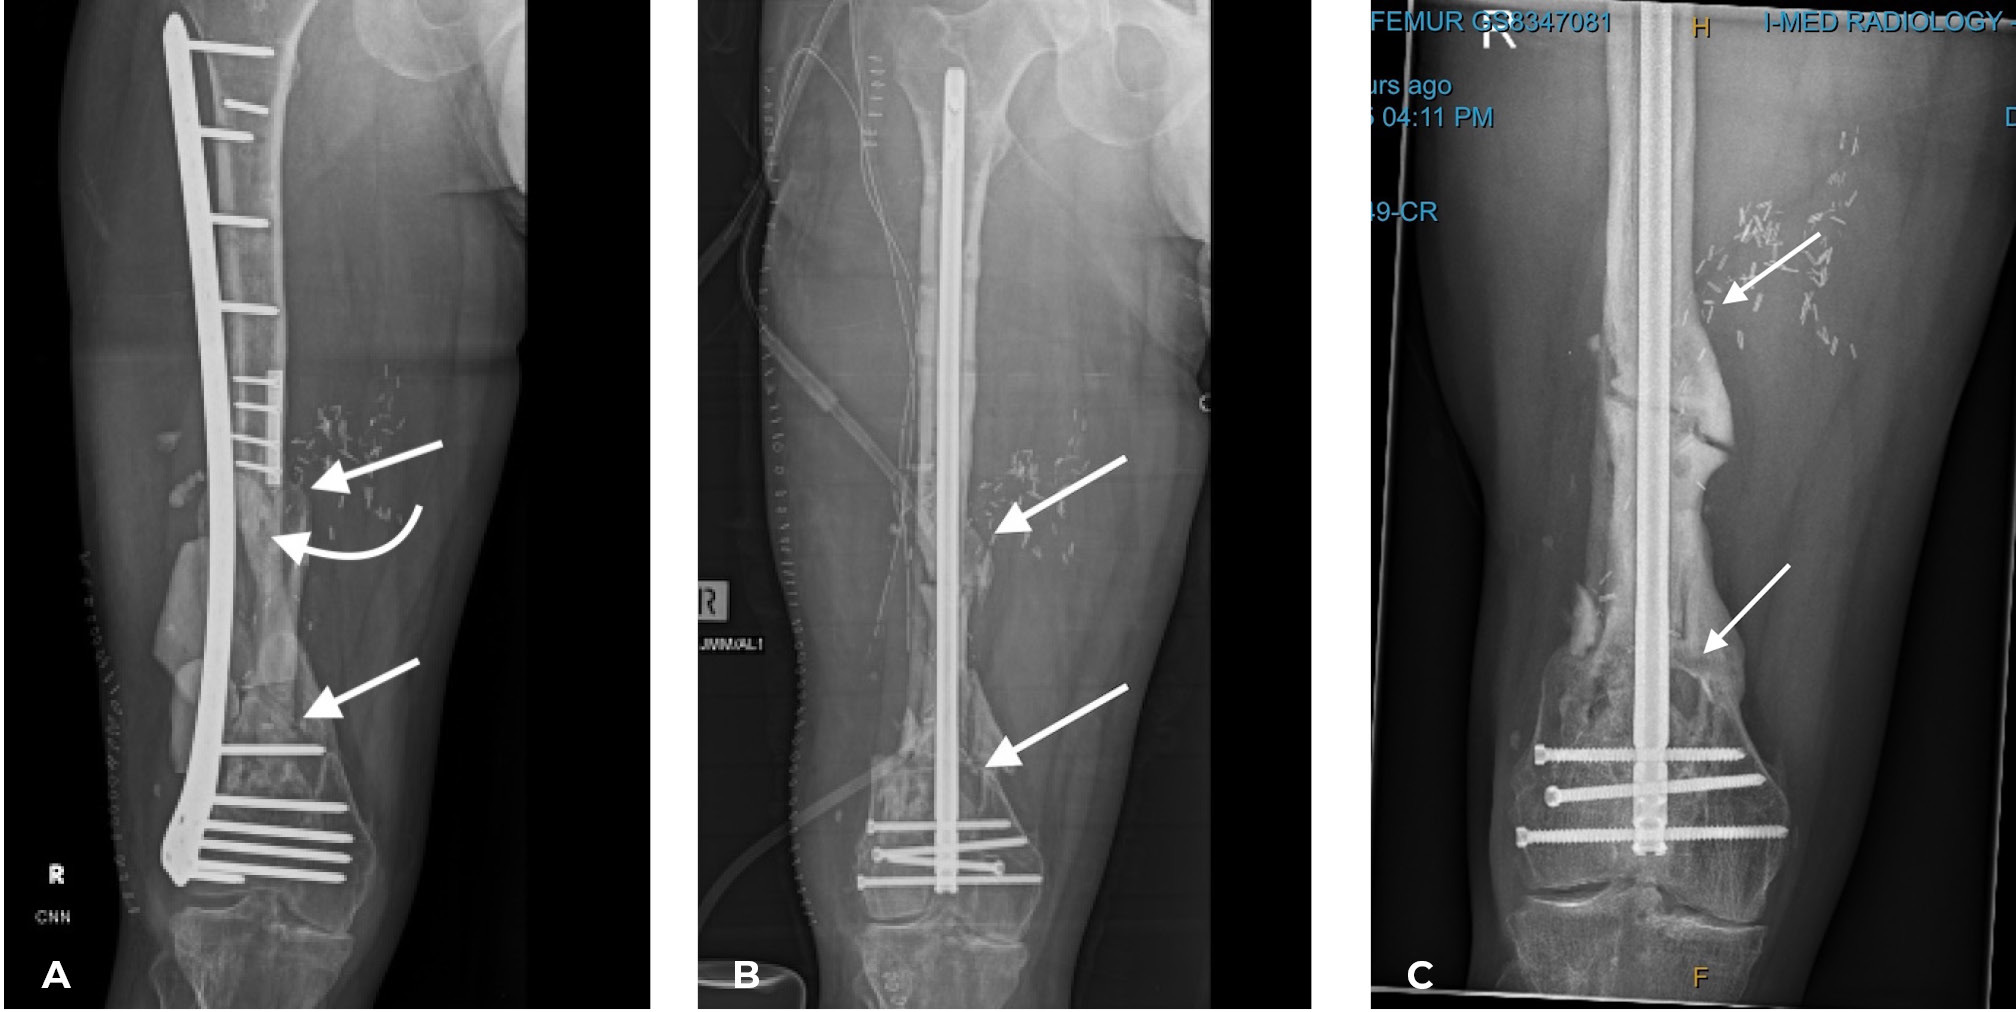

The importance of centralising the fibula within the medullary cavity of the femur or tibia is again reinforced by another case done at the Royal Melbourne Hospital. The fibula was used to reconstruct the femur but fixed rigidly with a plate and screws in Case 14 (Figure 34A). Twelve months later there was union but no sign of hypertrophy of the transplant. Then the plate broke. A Kuntscher nail was inserted from above and down through the medullary cavity of the fibula. It shattered forming a row of ‘bangles’ around the nail (Figure 34B). Two years later, having walked on his ‘box of bones skewered by the K-nail,’ he was located and the leg radiographed. Except for one level, there was union and hypertrophy of all bone bangles (Figure 34C).